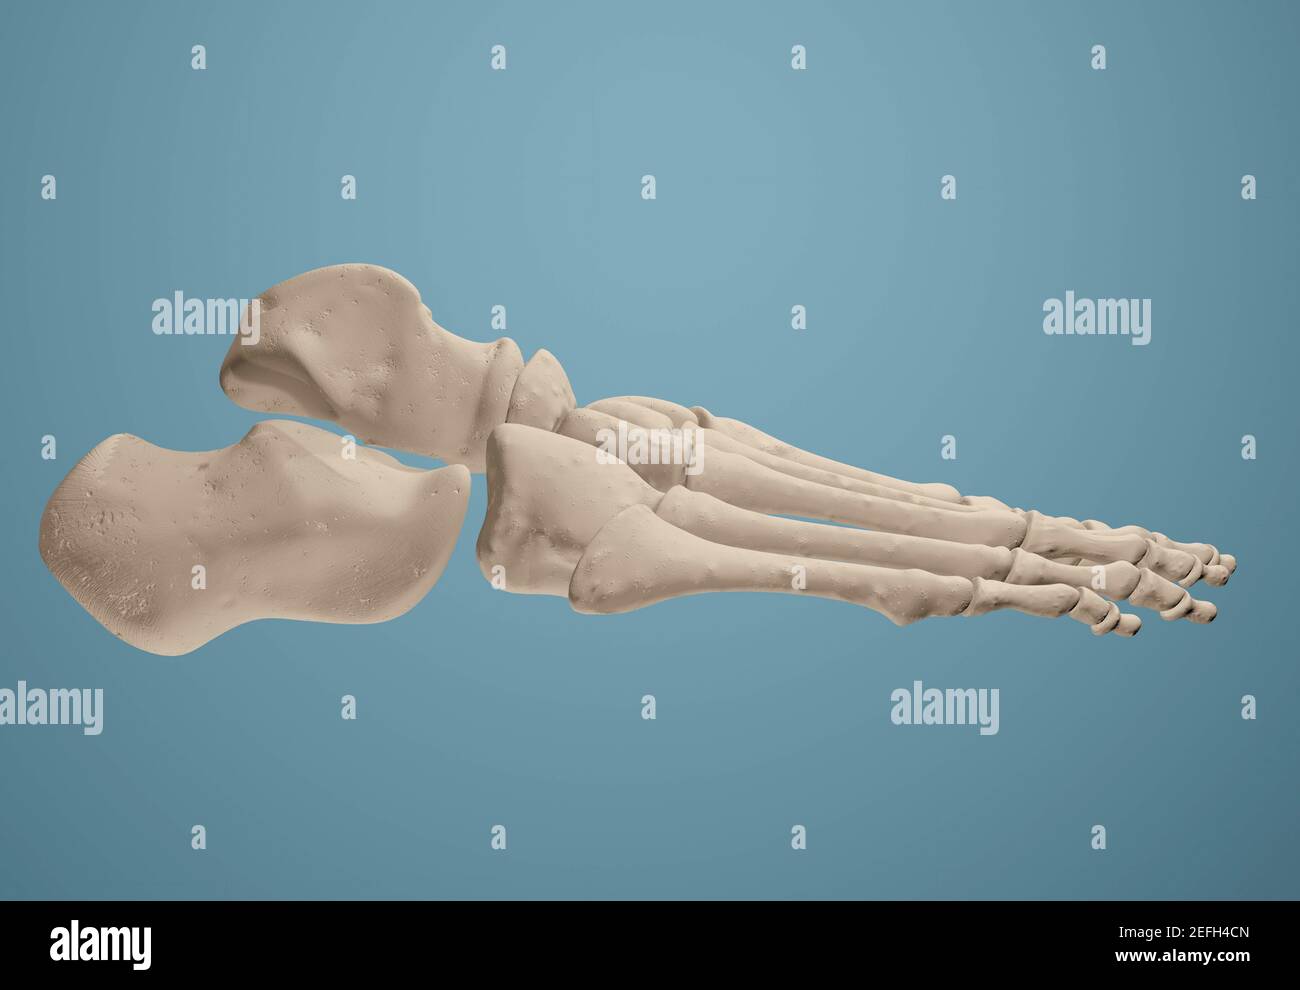

RF2R3WKY1–Illustration médicale des principales parties des os du pied en vue latérale, avec annotations.